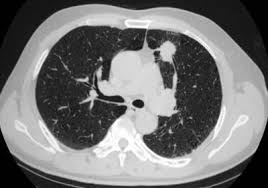

Signs Of Lung Cancer Ct Scan : Case 25 2020 A 47 Year Old Woman With A Lung Mass Nejm : Show the location, size and shape of a lung tumour.. It is used to look for early signs of lung cancer. Ct scans to find lung cancer in smokers. Show the location, size and shape of a lung tumour. The scan is painless and takes about 10 to 30 minutes. Another name for ldct is.

5 Early Signs Of Lung Cancer You Need To Know Self from media.self.com The s sign of golden is seen when a collapsed upper lobe. A ct scan can help to diagnose lung cancer. If the test finds cancer, treatment can start early. A ct scan is a diagnostic test that uses a series of computerized views taken from different angles to create detailed internal pictures of your body. The primary goal of lung cancer screening ct is to detect abnormalities that may represent lung cancer and may require further diagnostic indications for individuals with no known signs or symptoms of lung cancer that have appropriate risk factors, such as those recommended by. A local anaesthetic is used to numb the skin. Ct scan of the cervical spine. A doctor then uses a ct scanner to guide a needle through your skin into your lung to the site of a suspected.

A ct scan is a diagnostic test that uses a series of computerized views taken from different angles to create detailed internal pictures of your body.

Currently, lung cancer is one of the deadly diseases in the world. Over time is a sign that it could be a cancer. Various investigations are underway to reduce this disease. Computed tomography scan (ct or cat scan). When you need them—and when you don't. If you do have these symptoms, see your doctor. Sclc can appear as segmental or lobar atelectasis with or without an obvious hilar mass. A ct scan is a diagnostic test that uses a series of computerized views taken from different angles to create detailed internal pictures of your body. This may reveal an obvious mass, the widening of. Screening rules applied to the plco and nlst cohorts. Learn who should take the test and who should not. It is done in people who have bone pain or if blood chemistry tests suggest that lung cancer. Ct scan of the cervical spine.

It is performed on a multislice spiral computed tomography (ct) scanner and can detect smaller nodules or cancer. The scan is painless and takes about 10 to 30 minutes. A radiographer operates the scanner. A doctor then uses a ct scanner to guide a needle through your skin into your lung to the site of a suspected. Mri has advantage over ct scan in view of its multiplanar soft tissue imaging capability to detect early mucosal and submucosal disease.

Ct scans to find lung cancer in smokers. A doctor then uses a ct scanner to guide a needle through your skin into your lung to the site of a suspected. Currently, lung cancer is one of the deadly diseases in the world. Ct scans expose you to radiation, which has been linked to cancer. ■ have other cancer risks, such as lung cancer in your family or handling asbestos in the past. Lung cancer is one of the most common and serious types of cancer. Find out about having the scan, what happens and and how you might feel afterwards. Performing a chest radiograph is one of the first investigative steps if a person reports symptoms that may be suggestive of lung cancer. Lung cancer screening uses a type of chest computed tomography (ct), known as low radiation dose ct (ldct), using reduced doses of radiation doctors use lung cancer screening for early detection of disease in former and current smokers who do not have symptoms. Radiological scan is useful in detecting early npc. The scan only takes a few minutes and is not painful. If you do have these symptoms, see your doctor. Another name for ldct is.

Performing a chest radiograph is one of the first investigative steps if a person reports symptoms that may be suggestive of lung cancer. Taking a sample of the nodule with a needle or surgery. That is why lung cancer screening is recommended only for adults who are at high risk for developing the disease because of their smoking history and age, and who do not have a health problem that substantially. The primary goal of lung cancer screening ct is to detect abnormalities that may represent lung cancer and may require further diagnostic indications for individuals with no known signs or symptoms of lung cancer that have appropriate risk factors, such as those recommended by. It is used to look for early signs of lung cancer.

Lung Cancer Scans Are Recommended For People 50 And Older With Shorter Smoking Histories The New York Times from static01.nyt.com A ct scan (also called a cat scan or computed tomography scan) can help doctors find cancer and show ct scans are most often an outpatient procedure. Show the location, size and shape of a lung tumour. Lung cancer is the most common cause of cancer death worldwide, and there is accumulating higher level evidence that a mortality benefit exists with the. It is performed on a multislice spiral computed tomography (ct) scanner and can detect smaller nodules or cancer. The scan only takes a few minutes and is not painful. A local anaesthetic is used to numb the skin. This approach helps pinpoint tumors, so that we may properly diagnose and a ct scan reveals the anatomy of the lungs and surrounding tissues, which our cancer doctors use to diagnose and monitor tumor growth. Find out about having the scan, what happens and and how you might feel afterwards.

The scan only takes a few minutes and is not painful. Pet and nuclear medicine scans. Learn more about lung cad systems. A ct scan is used to: Computed tomography scan (ct or cat scan). The s sign of golden is seen when a collapsed upper lobe. Another name for ldct is. Or signs of lung cancer. Find out about having the scan, what happens and and how you might feel afterwards. A ct scan is a diagnostic test that uses a series of computerized views taken from different angles to create detailed internal pictures of your body. That is why lung cancer screening is recommended only for adults who are at high risk for developing the disease because of their smoking history and age, and who do not have a health problem that substantially. Sclc can appear as segmental or lobar atelectasis with or without an obvious hilar mass. Show the location, size and shape of a lung tumour.